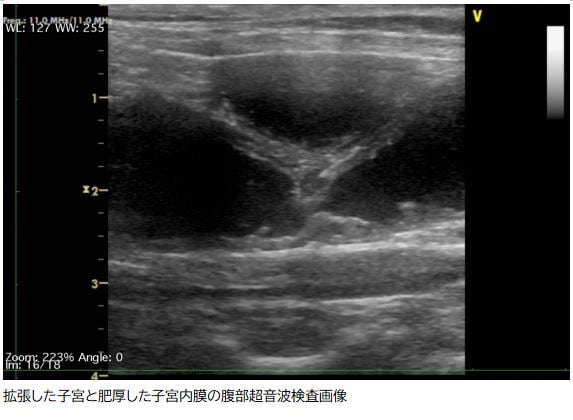

身体検査、血液検査、X線検査、超音波検査などから総合して診断します。特に超音波検査では分厚くなった子宮の組織や子宮内に溜まった液体が確認できるため非常に有用な検査となります。ただ超音波検査だけでは子宮内に溜まっている液体が膿かどうか完全に判断することが難しいため、血液検査やその他の検査で判断していきます。